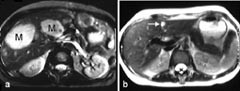

Vevsperfusjon er blodgjennomstrømning på kapillærnivå, oftest målt som antall milliliter blod per 100 g vev per minutt. Kapillarene er for små for visualisering med MR, men graden av perfusjon kan likevel avbildes. Den vanligst brukte teknikken er intravenøs bolusinjeksjon av et paramagnetisk kontrastmiddel, etterfulgt av raske bildeopptak som følger kontrastmidlets første passasje gjennom det aktuelle organ, f.eks. hjerne, hjerte eller nyre. Et perfusjonsopptak av hjernen gjøres gjerne med EPI-teknikk, og dette kan omfatte f.eks. 15 bilder av hjernen hvert andre sekund i totalt 100 sekunder, hvilket gir totalt 750 bilder. Evalueringen av dette store bildemateriale krever naturlig nok kraftige datamaskiner med egnet programvare. Etter opptaket kan man få en grafisk fremstilling av hvordan signalstyrken endrer seg med tiden under passasjen av kontrastmidlet, og basert på disse data kan man kalkulere og bildefremstille den relative mengde blodvolum i de ulike deler av hjernen (1) (fig 4a). Man kan også få avbildet hvor fort kontrasten når de ulike områdene, og dermed få visualisert områder med f.eks. forsinket blodstrøm (fig 4b). Det har imidlertid vist seg svært vanskelig å få en eksakt kvantifisering av perfusjonen med denne metoden. Perfusjons-MR med kontrastmiddel har vært mye benyttet til å evaluere akutt hjerneslag, ikke minst for å prøve å differensiere mellom områder med reversibel og irreversibel iskemisk skade (2, 3).

Det finnes også MR-teknikker for kvantitativ måling av perfusjon. Den mest lovende teknikken kalles ”spin labelling” (protonmerking) (4). Man kan f.eks. påvirke protonene i arteriene på halsen med en radiobølge. Disse ”merkede” protonene vil strømme med blodet og påvirke signalet i hjernevevet. Metoden har også vært benyttet til kvantitativ måling av perfusjon i myokard (5), nyrevev (6) og lunger (7).